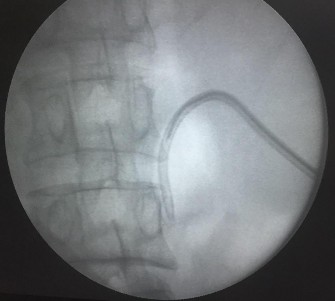

Hình 2.9. Đưa dây dẫn đường vượt qua viên sỏi (mũi tên) dưới kiểm soát của màn hình tăng sáng.

(Nguồn: chụp tại Bệnh Viện Trường Đại Học Y - Dược Huế)